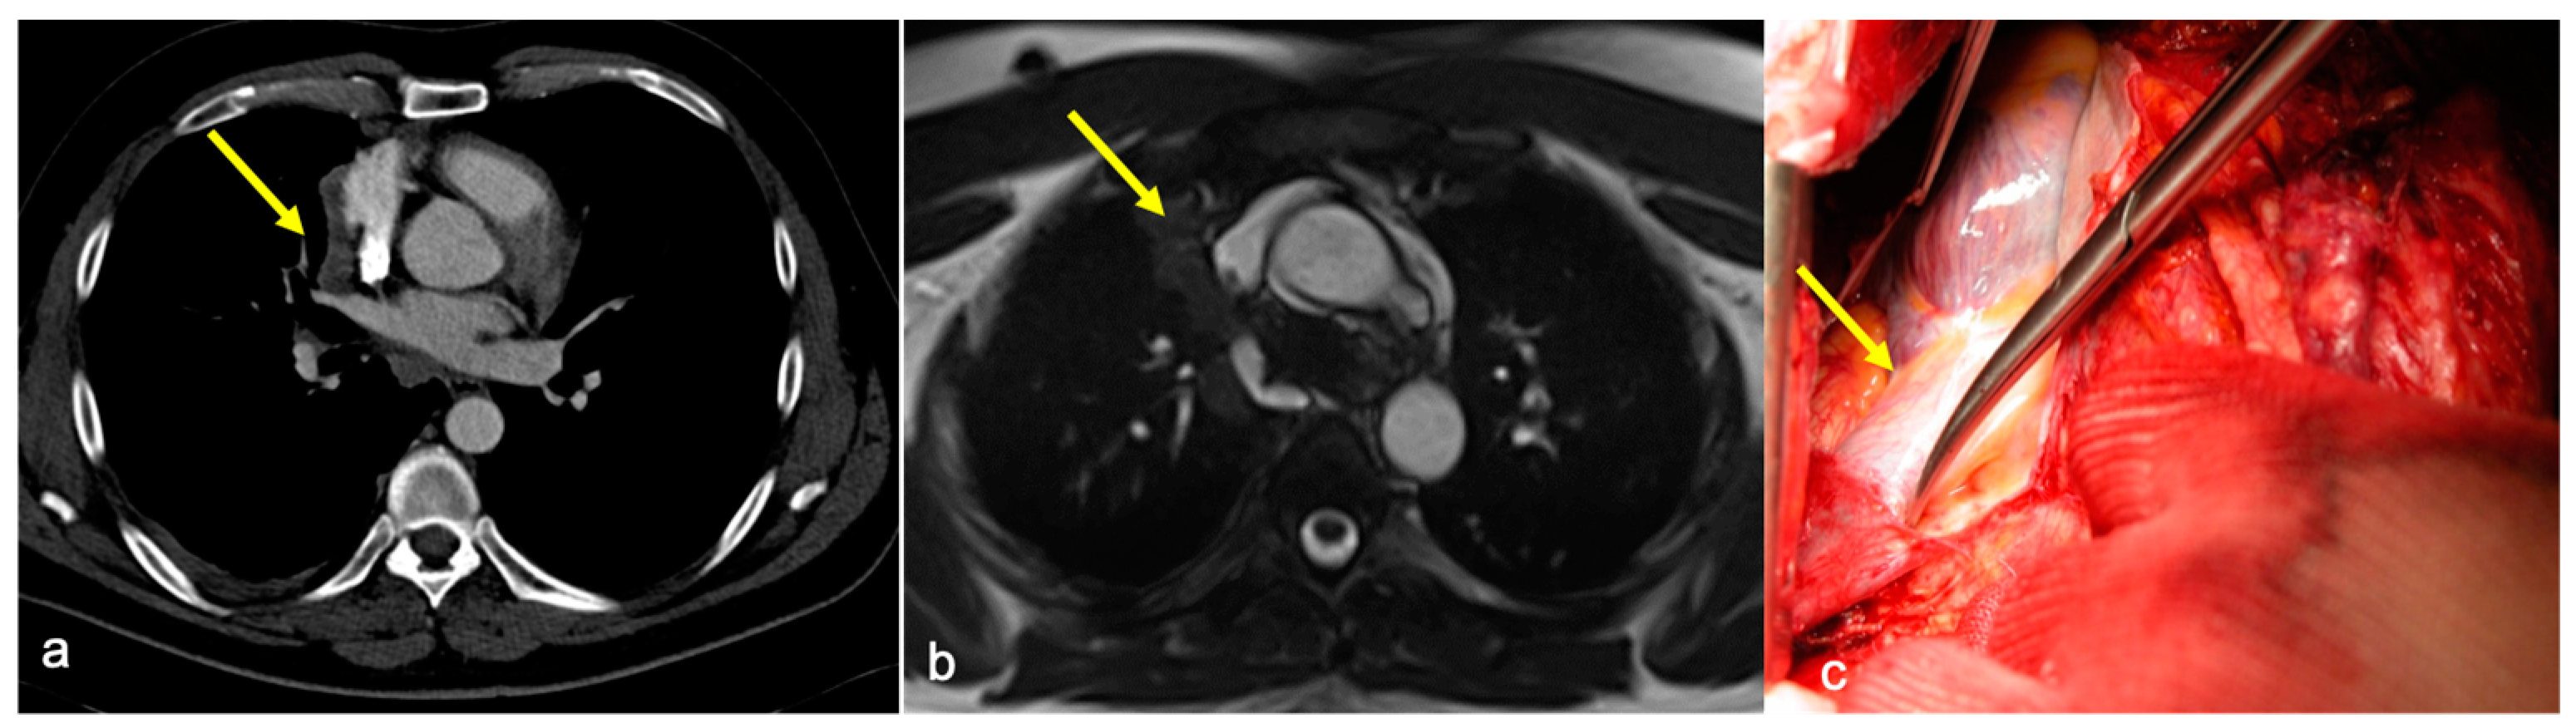

Infiltration was evaluated on the basis of the radiological reports of both CT and cine-MRI. On the contrast-enhanced CT scans, infiltration was reported when adipose tissue cleavage between the mass and the surrounding cardiovascular structures was absent. On cine-MRI, direct invasion was confirmed by the absence of the sliding motion between the mass and the heart and—for extracardiac sites—by the absence of the “India-Ink” artifact between the mass and the adjacent structures (Figure 1 and Figure 2). The surgical approach was defined after a multidisciplinary meeting where CT and MRI images of a single case were studied by radiologists and surgeons.

Figure 1. (a) Axial contrast-enhanced CT showing a fat cleavage between the ascending aorta and the tumor and (b) cine-MRI showing “India Ink” artifact between the two (yellow arrows). Infiltration of the aorta was absent at surgery.